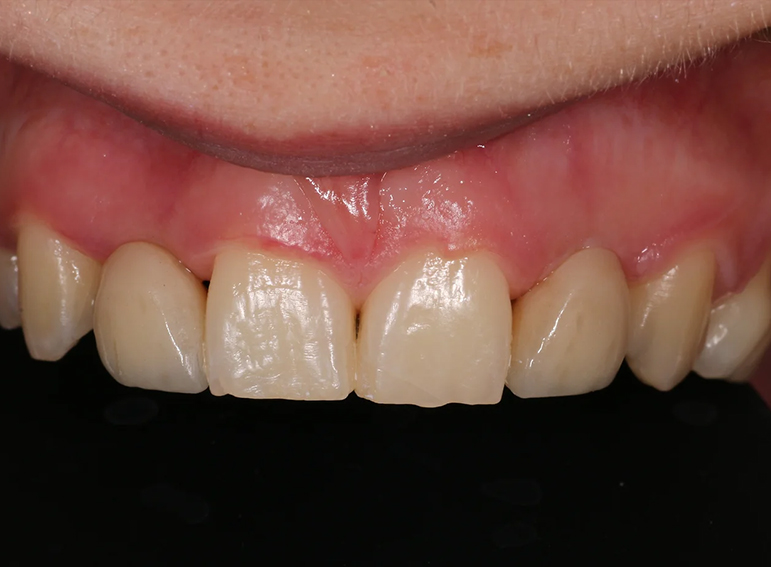

Gingival surgery and composite build up of an UR2 to resemble an UR1 following orthodontic treatment.